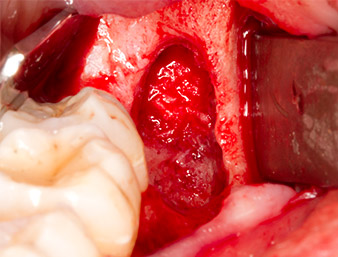

Sous bloc nerveux et anesthésie locale, le site d’intervention est ouvert et les tissus mous sont exposés afin d’accéder à la zone rétromolaire buccale (Fig. 3).

Le tissu recouvrant le reste radiculaire n’est pas entièrement ossifié et est essentiellement constitué de tissu de granulation modifié par l'inflammation (Fig. 4).